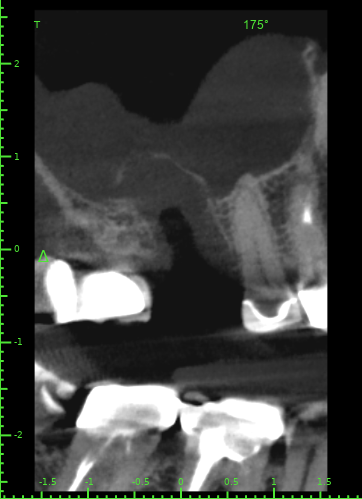

Atcotr Опубликовано 18 июля, 2024 Автор Поделиться Опубликовано 18 июля, 2024 @Женька @red_butler КТ сделано на 17-й день после удаления зуба. Не могли бы вы его посмотреть? Есть ли по вашему мнению свищ или признаки его формирования? Есть ли угроза для 27го импланта? Слизистая в гайморовой пазухе была опухшая задолго до удаления, это не новый процесс. КТ находится по ссылке: https://1drv.ms/f/s!AptB3I-32KWekuk4OkRq7Q6cdU7XcA?e=v69OYx Беспокоит чувство заложенности носа и уха слева после приёма любых жидкостей. Лечащий врач сказал, что небольшие перфорации в 95% случаев зарастают самостоятельно, назначил антибиотик и псевдоэфедрин и следующий приём через месяц. Спасибо за помощь. Ссылка на комментарий

Женька Опубликовано 19 июля, 2024 Поделиться Опубликовано 19 июля, 2024 Материала я, конечно, тут не особо вижу. Возможно он был, но весь вымылся. Перфорация действительно есть. Я бы ждал сейчас заживления и после оценивал формирование сообщения с пазухой. Снимок всю пазуху не вмещает, что там выше возле соустья неизвестно. Ухо, от ситуации на снимке, болеть вряд ли может на мой взгляд. Ссылка на комментарий